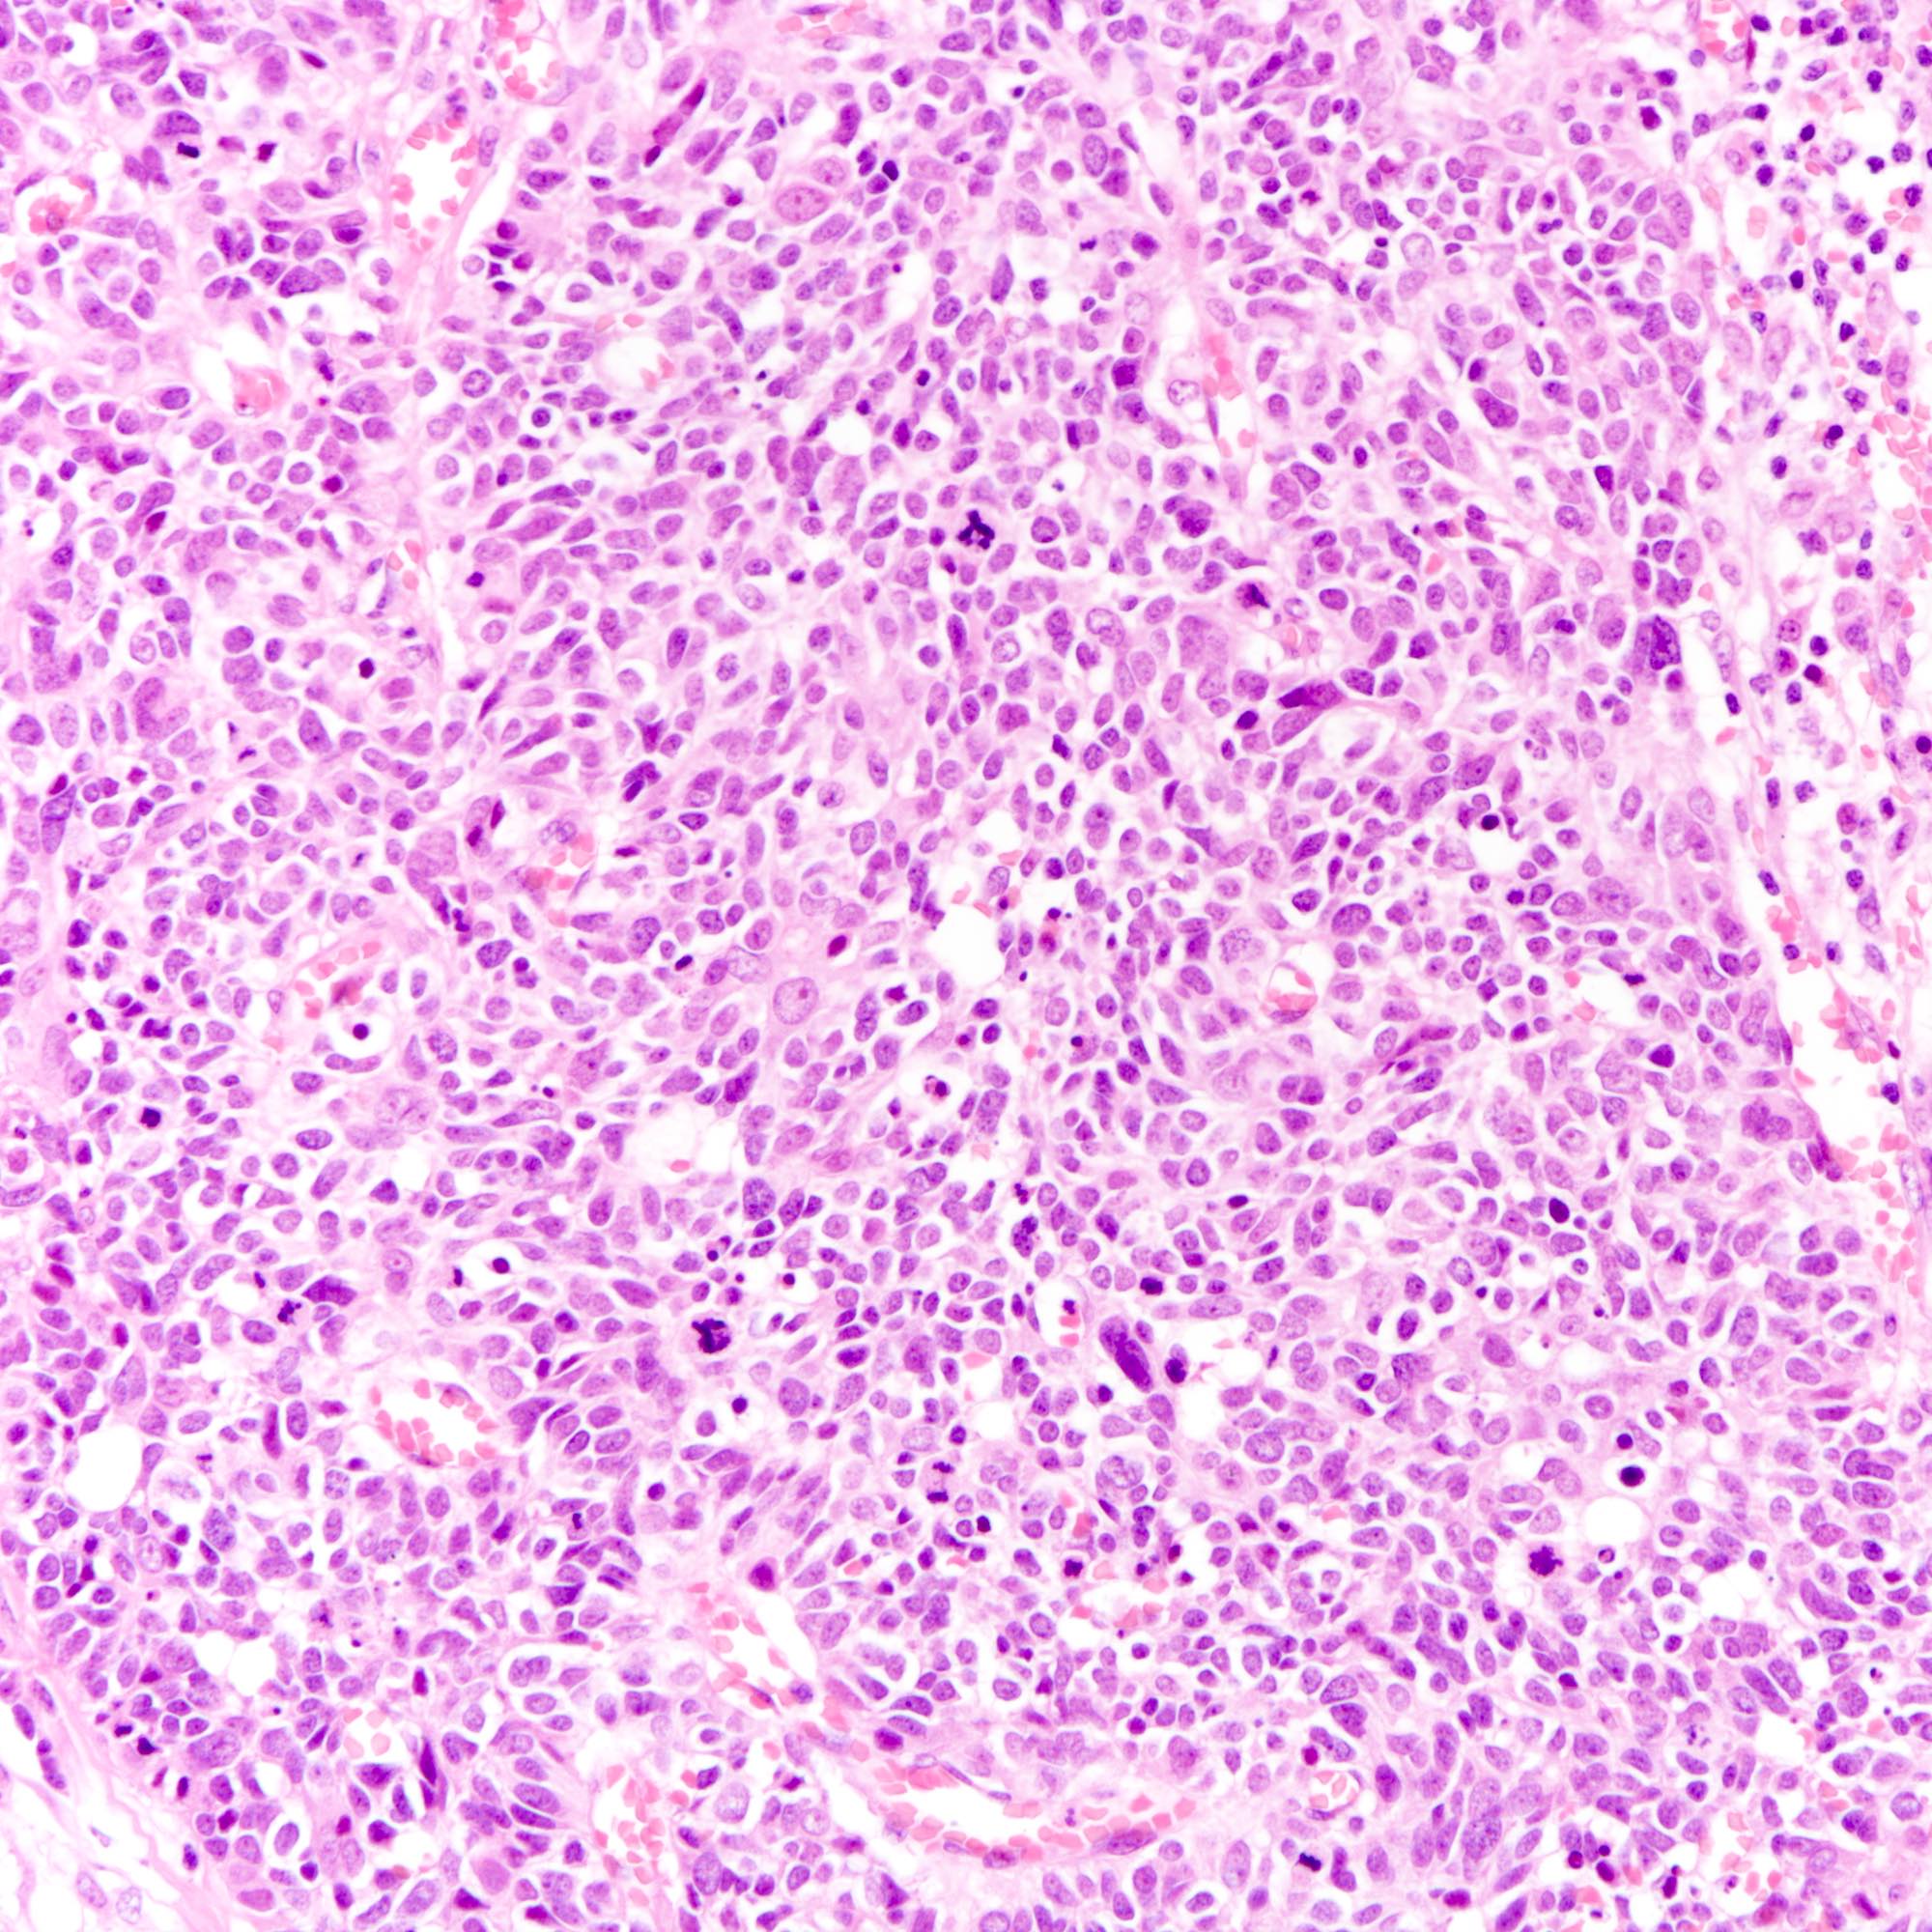

- Small cell carcinoma:

- Infiltrative growth pattern

- Crush artifact frequent

- Necrosis and lymphovascular invasion common

- Tumor cells densely packed with ill defined cell borders

- High N/C ratio with scanty cytoplasm

- Small dark hyperchromatic nuclei and inconspicuous nucleoli

- Mitotic count high

Microscopic (histologic) images

Contributed by Joshua J.X. Li, M.B.Ch.B., Gary M. Tse, M.B.B.S. and Kristen E. Muller D.O.

Small cell carcinoma